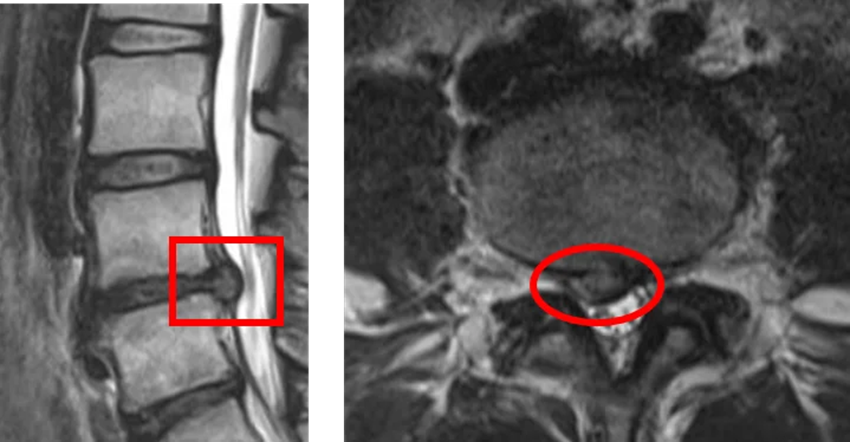

MRI画像での椎間板ヘルニア(左は矢状断からみた画像で、右は横断面からみた画像)

MRIの画像では腰痛の要因に関連している椎間板・神経・靭帯・関節部分の変形や神経への圧迫の状態や損傷の有無、炎症の有無などを確認することができます。

MRI画像は病変の範囲を明確に示すことができますので、正確な診断ができます。